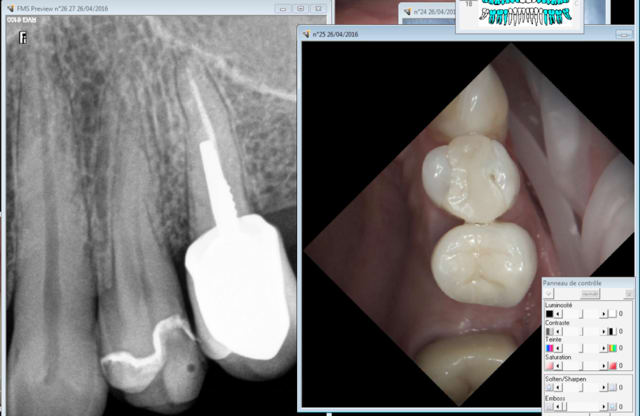

Aie 9 ans aussi. Ouh lalalala la cata. J'aurais du faire des radios après la pose il y a un binz en distal de la 36. -)))

Capture d e cran 2016 04 28 23.32 - Eugenol

Capture d e cran 2016 04 28 23.38 - Eugenol